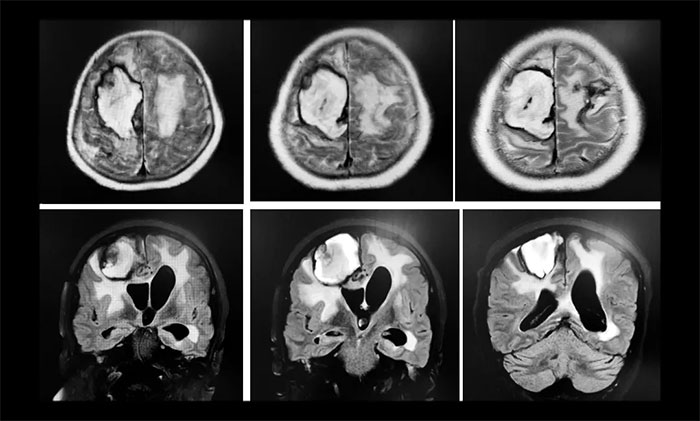

兩次癲癇發(fā)作后,王阿姨陷入昏迷,再也沒有醒來,并且生命體征不穩(wěn)定,上了呼吸機,體溫偏高,一直降不下來,醫(yī)院給予相關(guān)對癥治療,但未有好轉(zhuǎn),如此一直持續(xù)了20天左右。直到7月11號,在做了CT后,醫(yī)生發(fā)現(xiàn)腦占位,考慮腫瘤。“20天前,CT檢查什么都沒有,現(xiàn)在怎么會有腫瘤?”孫大叔提出質(zhì)疑。之后行MRI示右側(cè)額頂葉、基底節(jié)區(qū)及左側(cè)額葉、左側(cè)側(cè)腦室出現(xiàn)大面積積血、腦水腫;MRV示右側(cè)橫竇、乙狀竇、頸內(nèi)靜脈未見明確顯示。醫(yī)院影像科主任閱片后考慮靜脈竇血栓。而此時距王阿姨發(fā)病已經(jīng)過去了20天,錯過了介入取栓時間窗,只能選擇保守治療。在住院治療 42天后,王阿姨意識仍未恢復(fù),還出現(xiàn)肺部感染,之后她輾轉(zhuǎn)了多家醫(yī)院。

▲ 入院時,行頭顱MRI示:靜脈竇血栓導(dǎo)致右側(cè)額頂葉、基底節(jié)區(qū)及左側(cè)額葉大面積出現(xiàn)腦積血、腦水腫